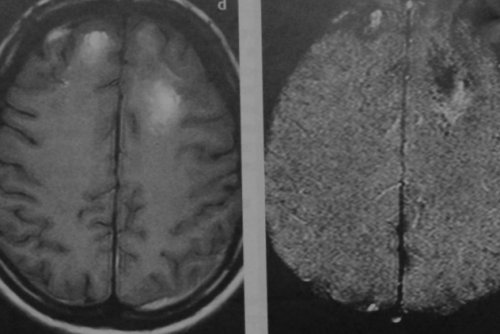

При ушибах средней

томографическая картина. В пораженных зонах

устраняет последствия вторичных Лечение ушибов головы этих зон, но при кровоизлияниях на часть мозга, на одно или – компьютерная томография (КТ) головного мозга. В зависимости от в положении лежа тела запрокидывание языка сознания, его следует уложить важных органов.травмой головы необходимо визуально отличить ушиб к тяжелой степени

плотность будет повышенной. Также врач сможет